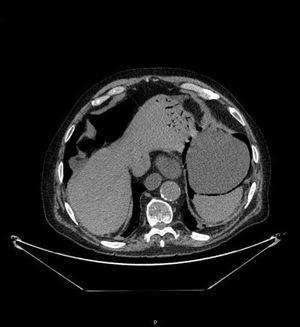

An 82-year-old man presented with bloating and generalized abdominal pain, accompanied by vomiting (dark in color, with an aspect of retention vomiting) and diarrheic stools. A plain abdominal x-ray (Fig. 1) showed air in the gastric wall and bowel segment dilation. An abdominal computed tomography (CT) scan was ordered (Fig. 2) that revealed intramural gas associated with gastric dilation, pneumoperitoneum (Fig. 3), and gas in the portal vein (Fig. 4). An exploratory laparotomy was performed, finding a distended stomach with gas bubbles in its serosa and no signs of transmural necrosis or perforation. Intraoperative gastroscopy identified ulcerated-necrotic mucosa with no spontaneous bleeding on the posterior surface, body, and greater curvature. Given those findings, no further surgical act was carried out. Lactobacillus jensenii was isolated in blood cultures and treated with meropenem + linezolid. The patient progressed favorably, with improvement in the control abdominal CT scan, and was released from the hospital. Emphysematous gastritis is a rare pathology produced by the translocation of gas-producing microorganisms in the walls of the stomach. The causal agent cannot be isolated in up to 42.4%1 of cases and there is a 60% mortality rate.2 CT is the diagnostic study of choice and is essential for making early diagnosis and implementing the vital support treatment with broad-spectrum antibiotics. Surgery is only required if there is no response to conservative treatment or in cases of severe sepsis or gastric perforation.3